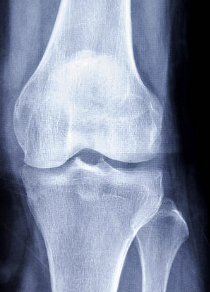

무릎 십자인대 파열 증상 및 십자인대 파열에 대해 알아보는 시간 갖도록 하겠습니다.

십자인대는 무릎 관절 내부에 있는 4개의 인대 중 하나로, 대퇴골과 승골 사이에 위치해 있습니다. 십자인대는 무릎 관절의 안정성을 유지하는 역할을 담당합니다. 무릎 관절에 직접적인 충격이 가해지거나, 무릎이 강한 스트레스를 받았을 때 십자인대가 손상되는 경우가 있습니다. 이러한 십자인대 손상은 스포츠 활동이나 사고 등으로 발생할 수 있습니다. 십자인대 손상 증상으로는 무릎 통증, 부종, 불안정감 등이 있으며, 심한 손상의 경우 수술이 필요할 수도 있습니다. 십자인대 손상을 예방하기 위해서는 적절한 스포츠화를 착용하고, 몸을 충분히 기르며, 스포츠를 할 때 안전장비를 착용하는 것이 중요합니다.